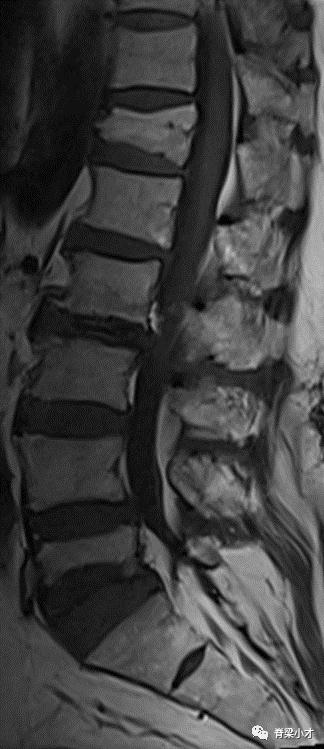

•腰椎休门病

休门病(Scheuermann’s disease)是青少年脊柱后凸的最常见病因,本病有家族性发病倾向,其遗传方式尚不明确,最新研究与COL9A3基因突变有关。近百年来人们对休门病的认识不断深入,但仍有不少尚待明确的问题。文献报告的患病率在1~8%不等,10~11岁之前几乎不会发现,12~13岁后可出现影像学改变。

腰背疼痛是最主要的症状,一般成年后可缓解。诊断主要通过医生查体并最终经X线检查确诊,典型诊断标准是在X片上连续3个椎体大于5°的楔形变,常存在许莫结节、终板不规则、椎间隙狭窄、椎体前后缘骨骺离断、椎间盘退变等。非典型休门病”的诊断存在争议;Blumenthal诊断标准:CT检查椎间隙狭窄、许莫结节和终板不规则3项中2项或核磁显示椎间隙狭窄、许莫结节、终板不规则、椎体楔形变和椎间盘信号减低5项中的3项即可诊断。有人将腰椎有此改变的称之为“腰椎休门病”。腰椎间盘突出症与腰椎休门病关系密切,腰椎休门病可能参与了腰椎间盘突出症的发病。